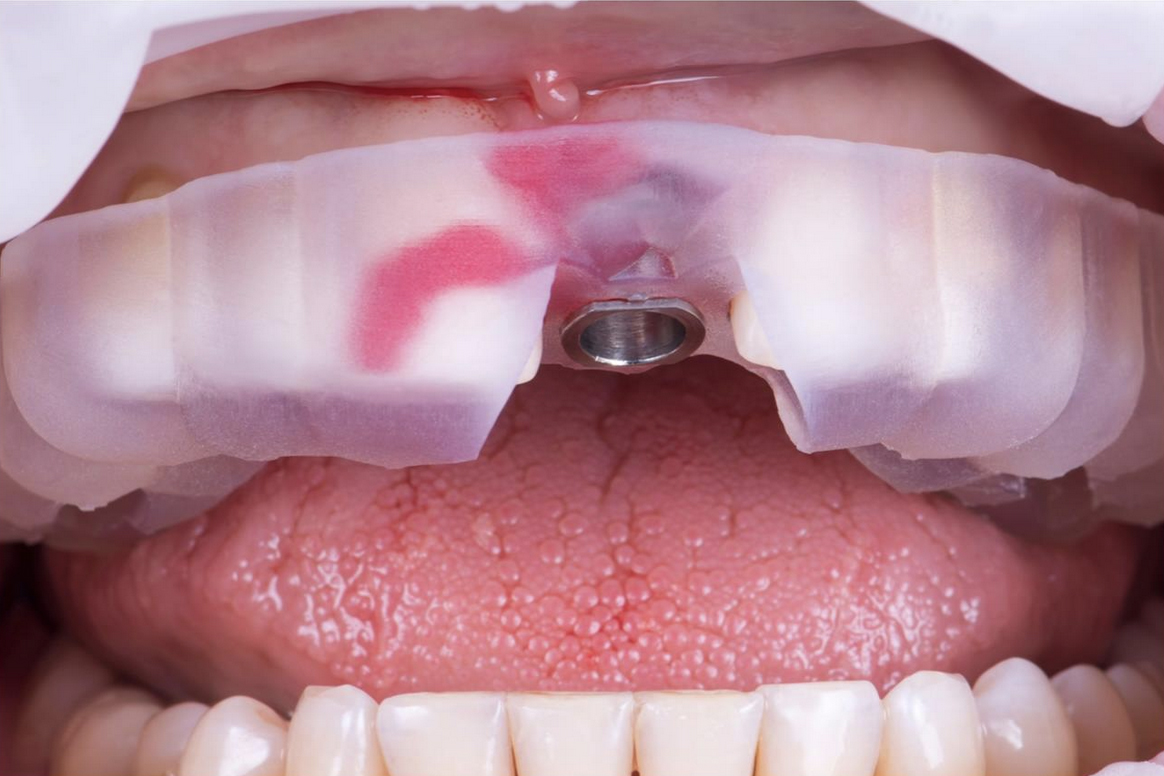

Cirugía guiada por ordenador con guías quirúrgicas

Cirugía guiada por ordenador con guías quirúrgicas.

La clínica dispone de un TAC que junto a un software permite al odontólogo la planificación de la cirugía y la elaboración de una guía. Con esta guía, es posible realizar la colocación del implante sin necesidad de abrir ni dar puntos, por lo que el postoperatorio es sencillo y sin complicaciones.